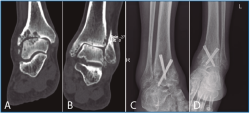

La segunda artrodesis se llevó a cabo durante el año siguiente a la primera intervención. La artrodesis fue tibioastragalina bilateral en 2 pacientes y tibiotalocalcánea (TTC) bilateral en el paciente restante. La estabilización ósea se realizó en un caso con 2 tornillos canulados Acutrak Plus® (Acumed, Hillsboro, EE. UU.) cruzados en ambos tobillos (Figura 1), en otro caso con clavo endomedular retrógrado T2 12 × 200 mm (Stryker, Schönkirchen, Alemania) en ambos tobillos (Figura 2) y en el último caso se utilizaron tornillos canulados Acutrak Plus® cruzados en el tobillo izquierdo y la técnica Putti en el tobillo derecho (Figura 3). La fijación de la artrodesis se realizó con el pie en plantígrado.

Figura 2. Caso 2. Varón de 58 años con artrosis bilateral de tobillo postraumatismo. Radiografía anteroposterior (A) y lateral (B) de tobillo derecho e izquierdo (C-D) preoperatoria. Radiografía anteroposterior y lateral de tobillo que muestra artrodesis tibiocalcánea de tobillo mediante clavo endomedular derecho (E-F) e izquierdo (G-H) a los 3 años de la última intervención (tobillo derecho). En las radiografías (E-H) muestra una consolidación parcial de la artrodesis sobre todo en la parte anterior de la articulación tibioastragalina que no se trató al ser asintomática.